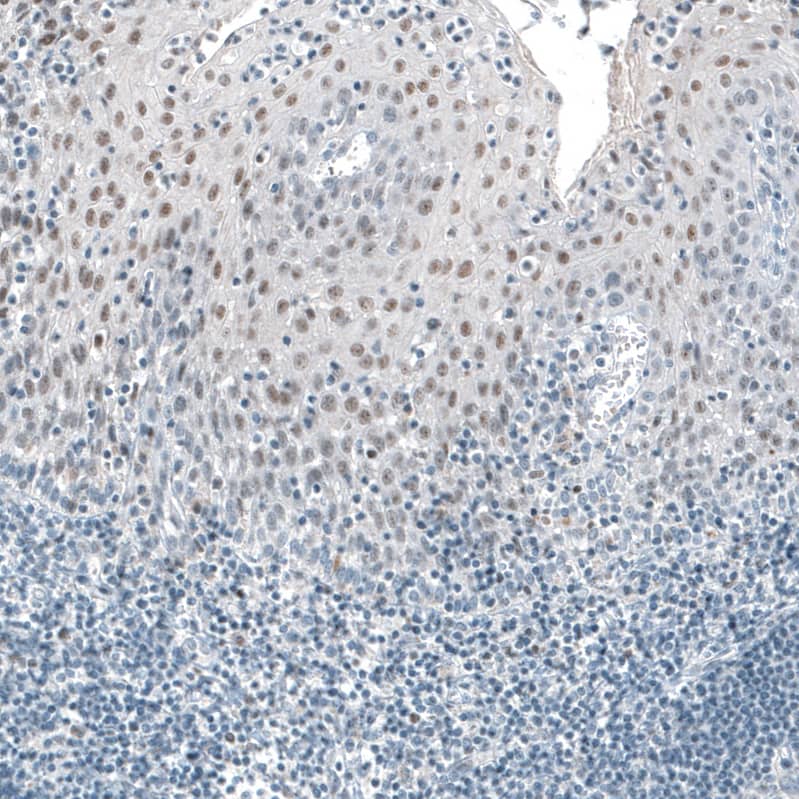

TET2 Antibody (CL6873)

NBP3-52056

Applications:

WB, ICC/IF, IHC

Host:

Mouse Monoclonal